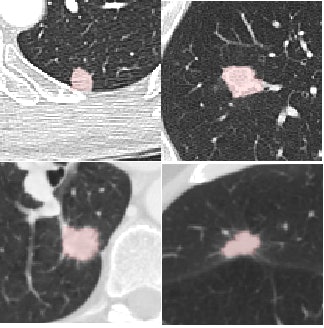

The study used CAD to analyze CT scans of the 108 LIDC subjects acquired with slice thicknesses and reconstruction intervals ranging from 0.5 mm to 3.0 mm (mean 2.1 mm), mAs ranging from 75 to 300, and kVp ranging from 120 to 140. The investigators chose a wide variety of nodules types from the LIDC database to show the range of nodule types detected in practice. Samples varied in size (from small to large), shape (including round, irregular, speculated, and cavitated), and connectivity from isolate to contacting vessels and pleura. Scanner manufacturers included GE Healthcare, Siemens Healthcare, and Toshiba Medical Systems.

The detection results showed that median sensitivity per subject was 100% (± interquartile range [IQR] 37.5) for nodules 4 mm and larger. For nodules 8 mm and larger, median sensitivity per subject was 100% (± IQR 8.0). The concordance correlation coefficient between the CAD nodule diameter and the LIDC reference was 0.91, and for volume it was 0.90, the authors wrote.